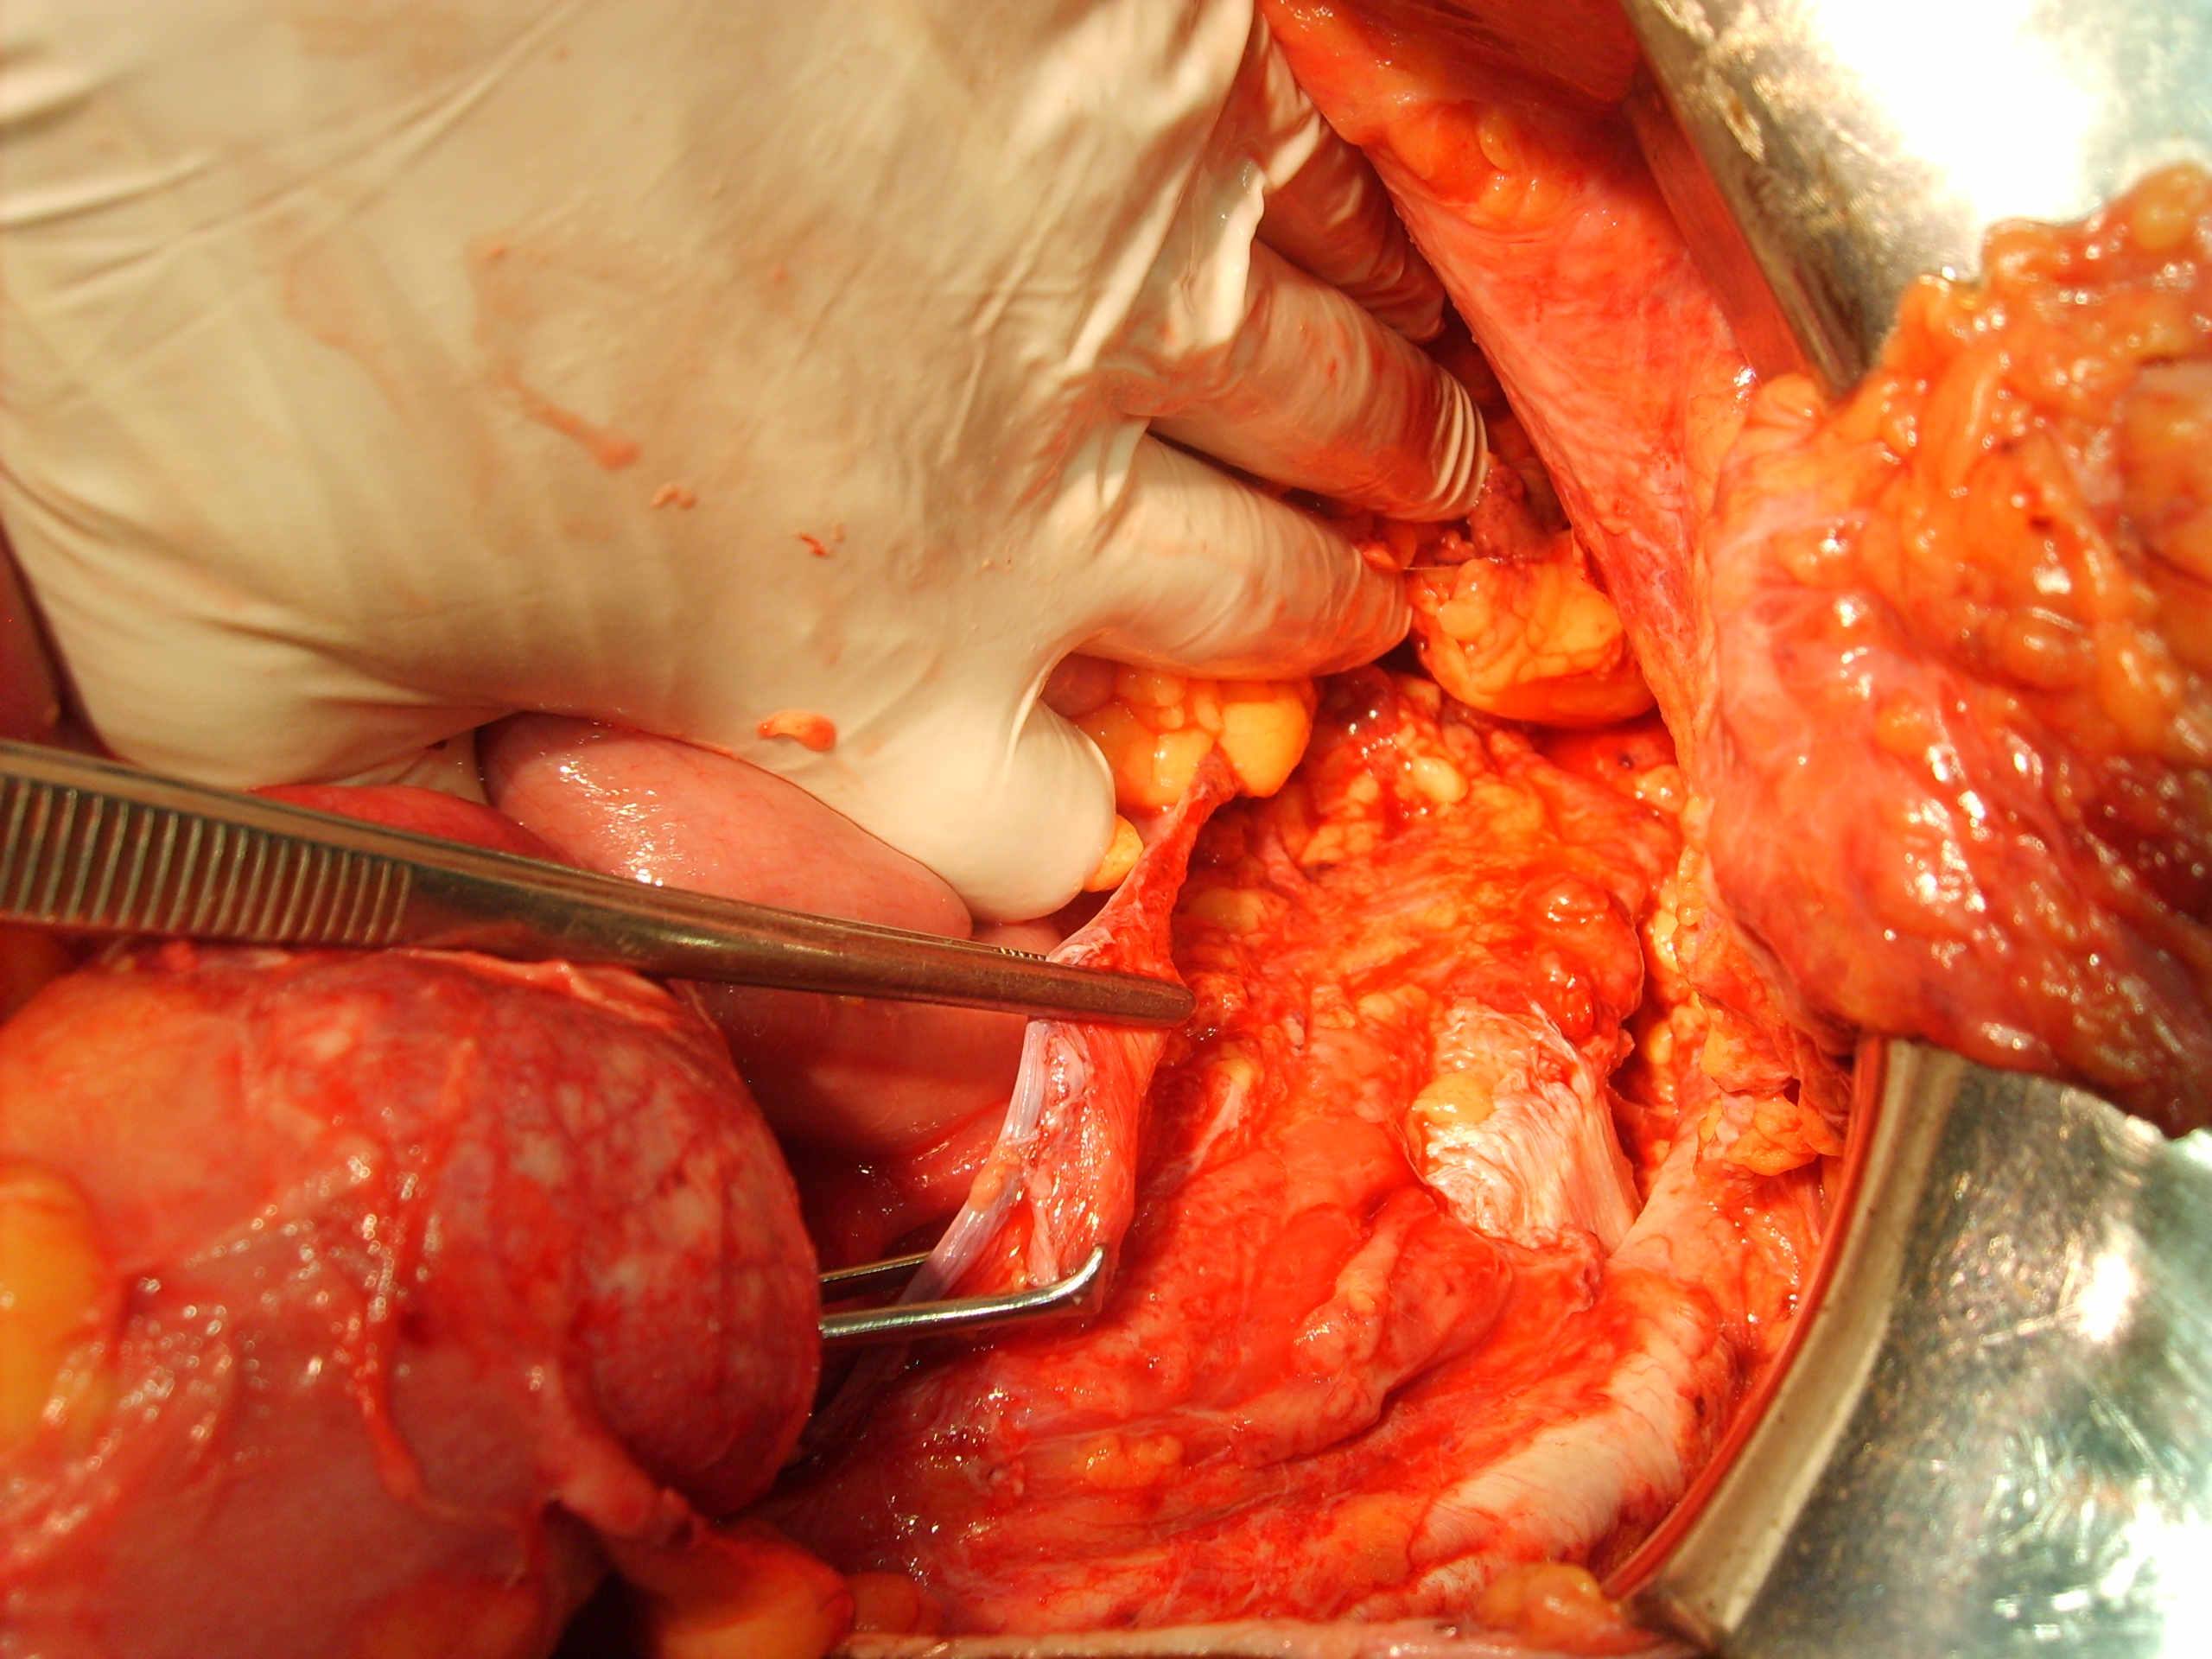

Paciente

Luego de estabilizada la paciente y al cuarto día de la cirugía del abdomen abierto se lleva la paciente al quirófano. Se constata abdomen con escaso liquido serohemático y asas intestinales sin compromiso vascular por lo que se decide cerrar el abdomen. Es dificultosa la tarea de contener las asas intestinales en la cavidad abdominal debido a la ausencia de pared lateral. Se decide el decolamiento del colon derecho e izquierdo a fin de lograr un espacio para colocar la prótesis, es decir generar un espacio real con el peritoneo para introducir la malla. La sugerencia adecuada del Dr Zorraquino es imposible de realizar, la enferma presenta una retracción importante de los músculos rectos que determinan una cavidad abdominal que supera ampliamente los 900 cm². Se coloca dos mallas de proceed 30 x 30 intraperitoneal fijadas con puntos al espesos total de los remanentes musculares y sobre la misma una malla de prolene 30 x 30 fijada abajo al pubis y a ambas crestas ilíacas y por arriba al plano aponeurótico de los rectos y Oblicuo mayor. Se deja piel y celular abierto. Vuelve a Cuidados Intensivos.

Interesantísimo caso el que nos presenta el Dr. Carlos Cano, bien iconografíado. Se ve en la última foto o así lo interpreto la sección de los músculos rectos y oblicuos.

Estimado Dr Reyes, aprecio tus comentarios, nosotros no disponemos de mallas biológicas, que si creo hubiesen sido de utilidad en este caso.Con respecto a colocar malla de polipropileno sobre la proceed, fué para tratar de darle más contención al contenido abdominal, por eso esa prótesis la fijamos al pubis y a las crestas ilíacas que estaban totalmente a la vista, según mostramos en algunas fotos.